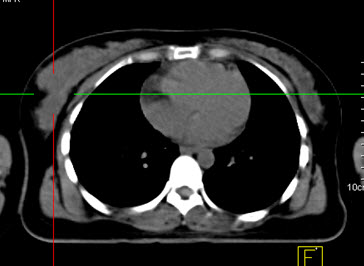

Hình 1. Bệnh nhân Phạm Th. X., nữ, 50 tuổi, bệnh nhân sờ thấy u nhỏ ở vú trái. Bệnh nhân được chụp PET/CT Hình PET/CT thấy khối u nhỏ ở vú trái tăng hấp thu FDG (mũi tên). Trên hình ảnh CT khó đánh giá được tính chất của tổn thương. Bệnh nhân được phẫu thuật và chẩn đoán là ung thư vú trái giai đoạn sớm.

(Nguồn: Mai Trọng Khoa – Trung tâm Y học hạt nhân và ung bướu – BV Bạch Mai)